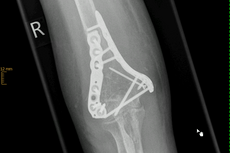

Distale Humerusfraktur

Der untere Anteil des Oberarmknochens bildet einen Anteil des Ellenbogengelenkes, auf dem sich die Unterarmknochen Elle und Speiche als Gelenkpartner bewegen. Frakturen in dieser Region müssen fast ausnahmslos operiert werden.